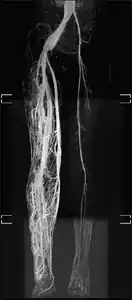

Angiogram: an angiogram can also be ordered to get a detailed look at the blood vessels in the affected or overgrown limb. In this test a physician injects a dye into the blood vessels that will help see how the blood vessels are malformed.[23]

MRI-dilated turtuous blood vessels

Angiogram